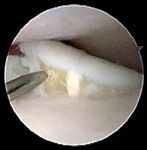

Further diagnostic tests to help differentiate causes of elbow pathology include arthrocentesis, imaging and arthroscopy. Radiographs are of little value in identifying the fragment or line of separation seen with classic FMCP or TFMCP (Photo 1). More advanced imaging techniques such as computed tomography, magnetic resonance imaging and arthroscopy may help confirm the condition. Arthroscopic evaluation of the elbow joint has the advantages of direct observation and magnification of all principal intra-articular structures, dynamic evaluation of tissues during range-of-motion exercises and palpation of intra-articular tissues with arthroscopic instruments. Consequently, arthroscopic exploration can help definitively diagnose TFMCP when a fragment or cartilage fissure is observed (Photo 2). In a small percentage of cases, advanced imaging (computed tomography, magnetic resonance imaging) indicates fragmentation of the coronoid not seen with arthroscopy. In such cases, the microcracks are thought to be within the coronoid bone beneath the cartilage surface.

Photo 2: An arthroscopic image of a dog with TFMCP.